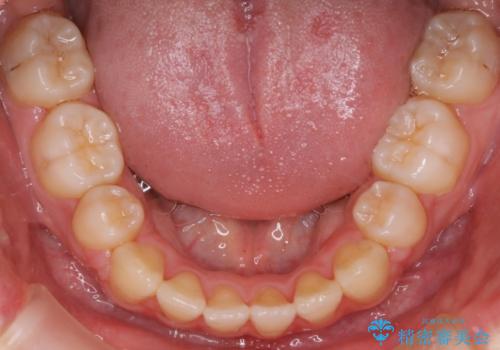

ワイヤーによる抜歯矯正でガタガタの改善

- 前歯のがたがたを主訴に来院されました。

上下の前歯が前方に傾斜しているのもあり、内側に前歯をひっこめるために上下左右の歯を1本ずつ抜歯して矯正することとしました。

ガタガタも改善しましたが、前歯が内側に引っ込むことにより口元もすっきりして、唇が閉じやすくなりました。